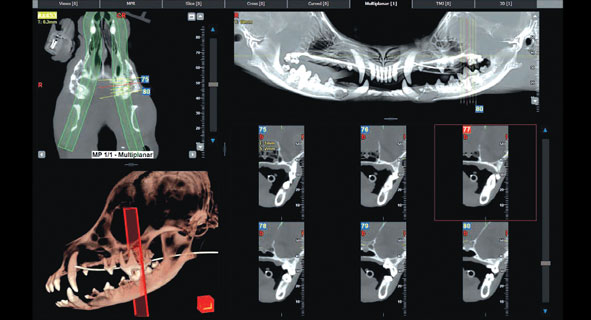

Новейший КЛКТ-аппарат с функцией мультисканирования тела, обеспечивает сверхвысокую чёткость изображений с разрешением до 90 мкм и адаптивным полем зрения от 4×4 см до 29×62 см. Он идеально подходит для исследования сложных областей, таких как суставы и микропереломы, и позволяет проводить как статический, так и динамический анализ.